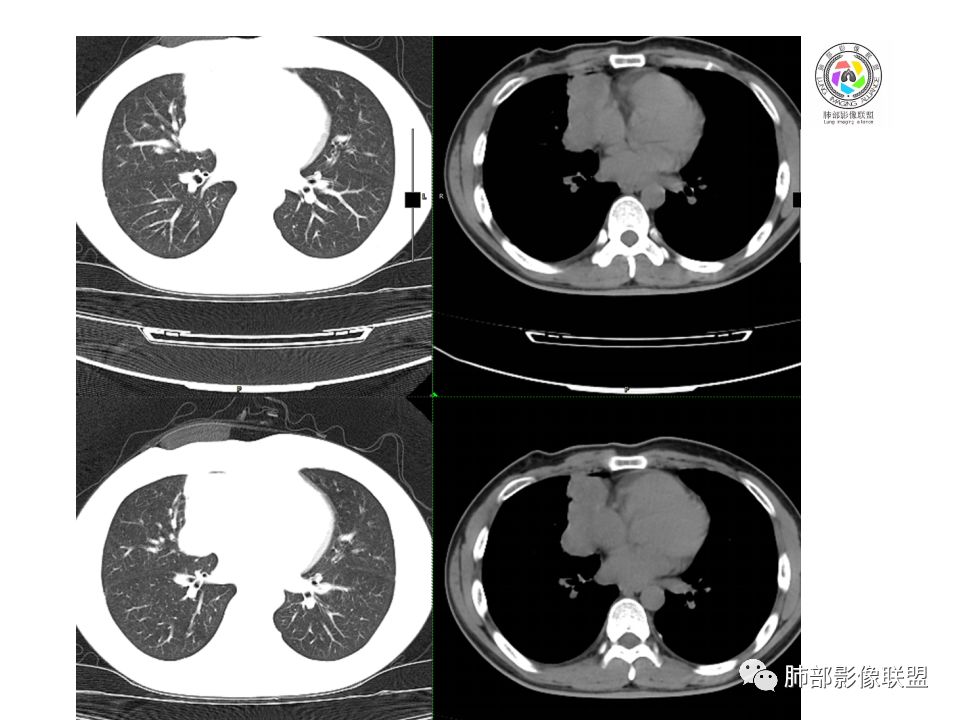

晨读:前纵隔占位,密度不均,沿着右侧纵膈延伸到肺门水平,周围支气管推移,大血管向内推移。临床有重症肌无力,考虑胸腺瘤可能,鉴别淋巴瘤。

患者青年人,前纵隔占位,无增强,猜一个淋巴瘤,不知道右下肺膨胀不全原因是什么

右前纵膈肿块,偏一侧生长,形态欠规则,密度不均匀,其内可见小点状钙化,双肺多发小叶中心结节及钙化灶,右侧胸膜增厚(有陈旧性结核可能),青年男性(27岁),没有增强,考虑,1,前纵隔生殖细胞瘤2,精源细胞瘤

右前上纵隔占位,瘤肺交界面清楚,提示纵隔来源,其内有点状钙化,右侧胸腔积液,有临床症状,年龄轻,考虑生殖来源可能,胸腺瘤待排,请结合临床相关检查或CT增强进一步检查。

前纵隔占位,伴点状钙化;上腔静脉后移位。伴右胸膜局限性增厚,临床有重症肌无力,病人年轻,考虑胸腺瘤可能,鉴别生殖源性肿瘤。

临床症状眼睑下垂,右纵膈占位,偏向一侧,有分叶,跟上腔静脉边界不清,淋巴结肿大,考虑胸腺瘤或胸腺癌

右前纵隔占位,有分隔`低密度、点状钙化,边缘光滑,侵袭心包不明确,伴右胸少量积水,考虑恶性,生殖源性可能大,有视物不清,是否脑转移待查。建议HCG丶AFP检查。鉴别1:胸腺瘤、癌,30一40岁以下,少见,但有眼脸下垂,肌无力,待排除。2:淋巴瘤:侵袭性不强,有点状钙化,不支持。3:畸胎瘤:有低密度丶钙化,建议增强进一步明确。4:神经源性:一般后纵隔常见,不支持。5:LCD:症状少见,可以有树枝状钙化,浆细胞型可以有低密度,增强进一步明确

前纵隔偏侧肿块,病灶内见点状钙化,症状肌无力,考虑恶性,胸腺瘤或神经内分泌癌

没有增强,好像两个病灶,上方三角形的像是胸腺增生。下方肿块,没有增强显得更难了,微钙化,轻度分叶,像有坏死低密度影,右侧少量胸水,胸膜受侵.,有视物模糊眼睑下垂。考虑胸腺瘤B1型及以上、B2型可能或生殖细胞瘤

患者年轻,有肌无力症状,除肿块外,前纵隔密度增高,与心包界限不清,考虑恶性。

前纵隔右区占位性病变,上区与胸腺延续,下区呈分叶状,尽管年龄<30还是首先考虑胸腺瘤,侵袭性可能性大(眼睑下垂不知是否有关)。鉴别主要是生殖细胞类肿瘤,主要是精原细胞瘤。另左肺上叶结核球,右侧胸腔积液,需除外结核性胸膜炎和转移

前纵隔占位性病变,偏向一侧生长,密度不均,可见点状钙化,考虑胸腺瘤,鉴别精原细胞瘤

右前纵隔肿块,边界清楚,密度欠均匀,内似有分隔和低密度区,似有多结节融合,几乎从上到下,年龄较轻,不是胸腺瘤好发年龄,但却有视物模糊,眼睑下垂症状,考虑淋巴瘤?鉴别胸腺瘤?结核?

右前上纵膈肿块,内有点状钙化和少许小片状坏死,局部边界似欠清,右侧胸膜腔少量积液,年轻男性,小于30岁,有重症肌无力,虽然年龄偏轻,仍先考虑胸腺瘤,代排生殖源性肿瘤

晨读前纵隔肿块,偏右侧,密度不均,见点状钙化灶及分隔状低密度影。胸腺瘤>生殖细胞瘤>淋巴瘤

前纵膈占位,上腔静脉受推移,有分叶密度较均匀,结合临床考虑胸腺瘤,待排生殖细泡瘤.淋巴瘤

前中纵隔(胸腺癌区)不规则肿块,密度不均,有坏死区、点状钙化,边缘不会整肿块偏向右侧,向心包流注感,右胸腔少量积水。患者27岁,重症肌无力表现。